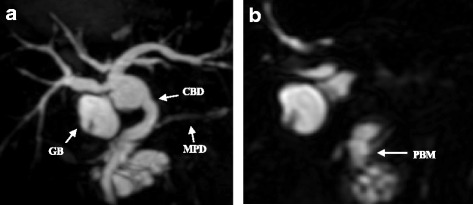

Computed tomography (CT) showed a low-density mass in the pancreatic head and thickness in the wall adjoining the gallbladder (Fig. 1a, b). Furthermore, lymph nodes around the pancreas were swelling and multiple cystic lesions with a mural nodule were found in the head of the pancreas. Magnetic resonance imaging (MRI) showed a partially cystic dilatation of the common bile duct, 32 mm in diameter, revealing that the pancreatic duct joined the common bile duct 24 mm above the papilla of Vater. The cystic dilatation of the common bile duct was classified as type Ia using the Todani system [ref. 14], and a cystic lesion in the head of the pancreas was confirmed as a branch duct-type intraductal papillary mucinous neoplasm (IPMN) (Fig. 2a, b). Positron emission tomography (PET)-CT showed an abnormal accumulation of 18-fluorodeoxyglucose (FDG) in the pancreatic head and gallbladder. The patient rejected invasive examination: therefore, we did not performed endoscopic ultrasonography (EUS) or Endoscopic retrograde cholangiopancreatography (ERCP) preoperatively.